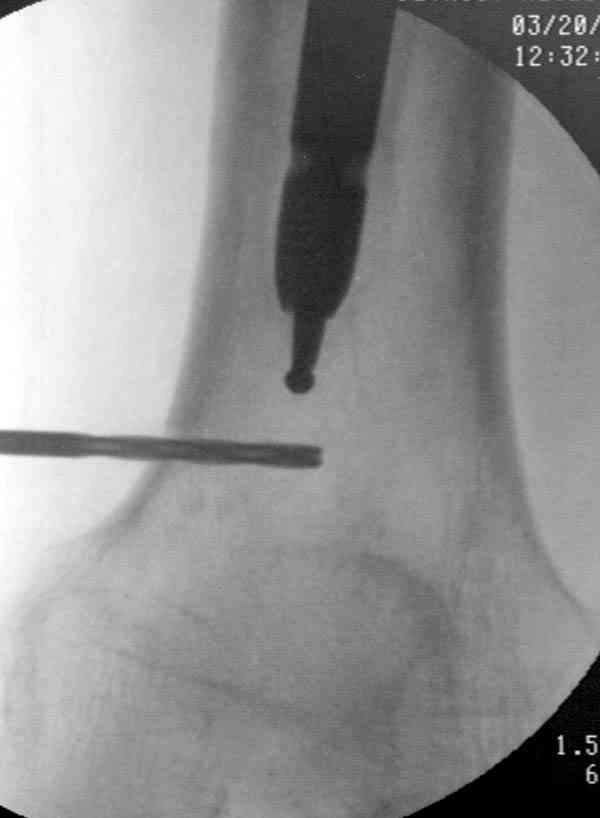

Какой из вариантов лучше, коллеги? Еще какие варианты возможны? Есть у кого-нибудь опыт закрытого удаления поломанного штифта с учетом наличия ЭОП-а?Заранее благодарен за ваше мнение!

Периферический отломок стержня - наверно, надо воспользоваться отверстием, над ним сделать трепанацию и через него вверх провести длинную спицу, сделав на ее нижнем конце крючок. Лучше уже перед этим рассверлить центральный отломок.

Приспособление для удаления сломанных штифтов и наличие ЭОП облегчит задачу. При отсутствии крючка тогда можно применить обычный длинный ball pointed guide wire от интрамедулярного набора. Проволока, пропущенная за пределы гвоздя и зажатая другая вытащат сломанный конец штифта без проблем.